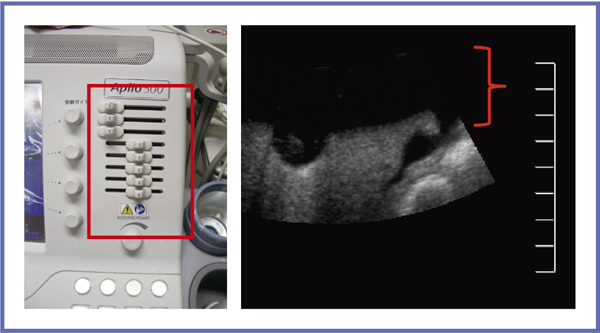

■Smart Fusion

Smart Fusionは,リファレンスとなるCTあるいはMRIの画像と超音波画像を対応させて位置情報を共有することで,腫瘍の同定,位置認識を支援するシステムである。映像処理は磁気の送受信により行われるが,Aplio 500は送信機(磁場発生装置)が装置に一体化しており,伸縮するアームを取り出すだけで非常に簡便である(図11a)。また,受信機は非常に小さく,プローブのケーブルの根元に装着するだけであり,通常の操作も違和感なく行うことができる(図11b)。

図11 Smart Fusionの送受信機